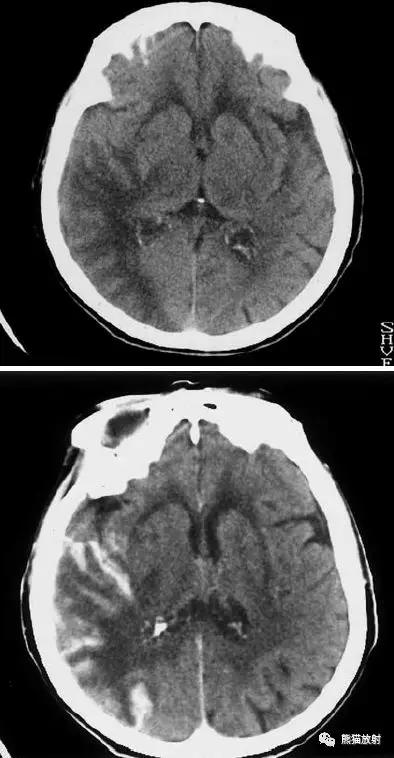

右侧大脑中动脉区域梗死的典型演变:

a)急性期

b)早期亚急性期(2天,从临床起病开始)

c)亚急性晚期(2周后)

d)慢性期(一年后)